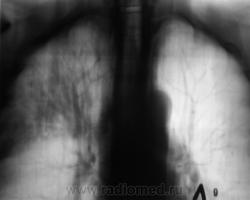

Пациент 4 месяца, по полной программе отлежал в областной конторе, ЦВК утвердило «инфильтративный». После выписки был направлен под надзор фтизиатра по месту жительства. Ниже иллюстрации после выписки.

Снимки сегодня.

Хорошая динамика, практически все рассосалось.

На мой взгляд на "семерке" еще дай-дай...